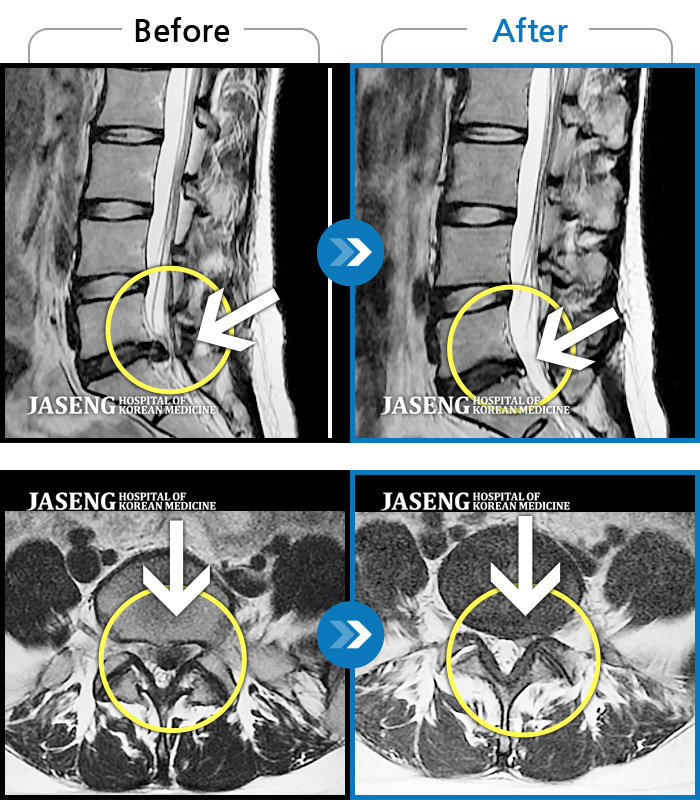

Before

After

환자에게 사전 동의를 받아 동일 조건에서 촬영되었습니다.

개인에 따라 치료 후 부작용이 발생할 수 있으니 의료진과 상담 후 치료를 진행하시기 바랍니다.

오래 앉아 있으면 오른쪽 아래 허리 통증 심화

허리디스크로 인한 허리통증